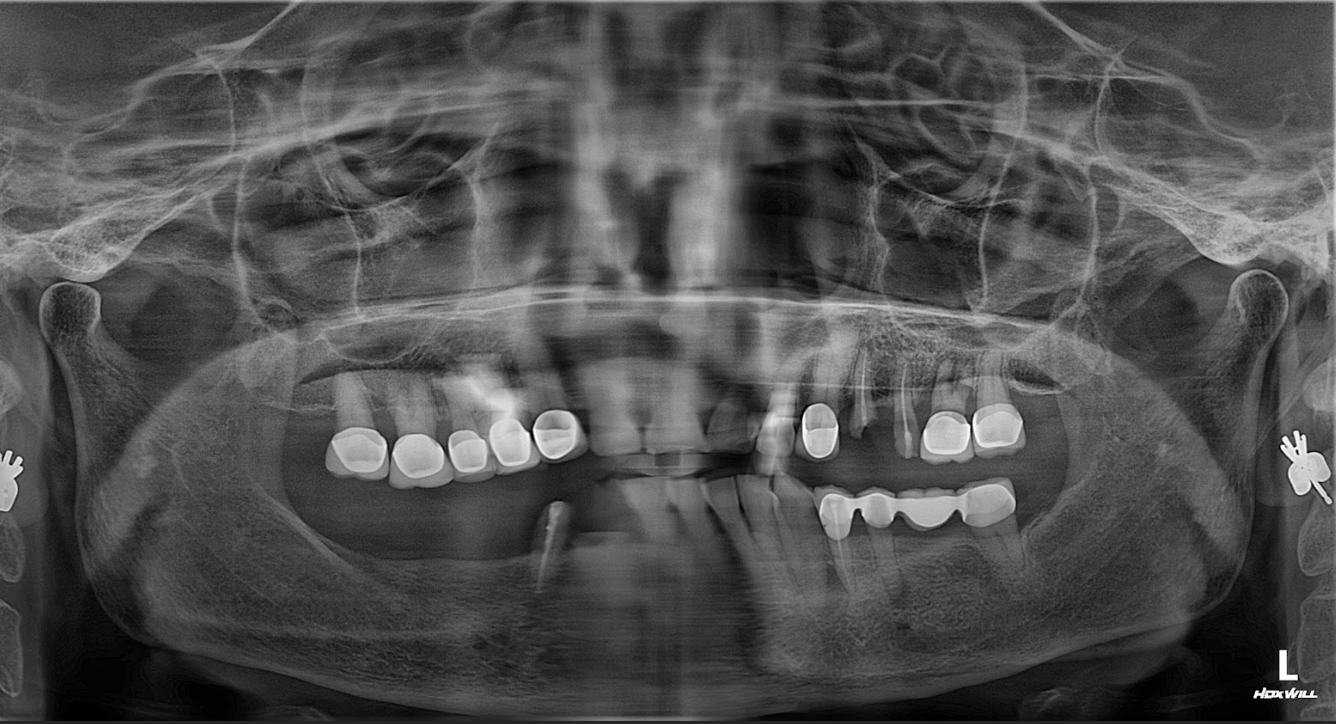

Tình trạng răng của cô Phương trước khi điều trị

Mất gần như toàn bộ răng hàm trên và hàm dưới.

Đã từng làm cầu răng tháo lắp, nhưng nhanh chóng hỏng và gây đau nướu.

Không thể ăn nhai thoải mái, phải lựa chọn thức ăn mềm, ảnh hưởng nghiêm trọng đến sức khỏe tiêu hóa.

Nụ cười gượng gạo, tâm lý mặc cảm khi giao tiếp.

Sau nhiều năm chịu đựng, cô quyết định tìm giải pháp trồng răng Implant để khôi phục chức năng ăn nhai và nụ cười.

1. Khám & chẩn đoán

Thực hiện chụp CT ConeBeam 3D để đánh giá mật độ xương hàm.

Phân tích tình trạng tiêu xương do mất răng lâu năm.

Đưa ra kế hoạch trồng Implant toàn hàm.